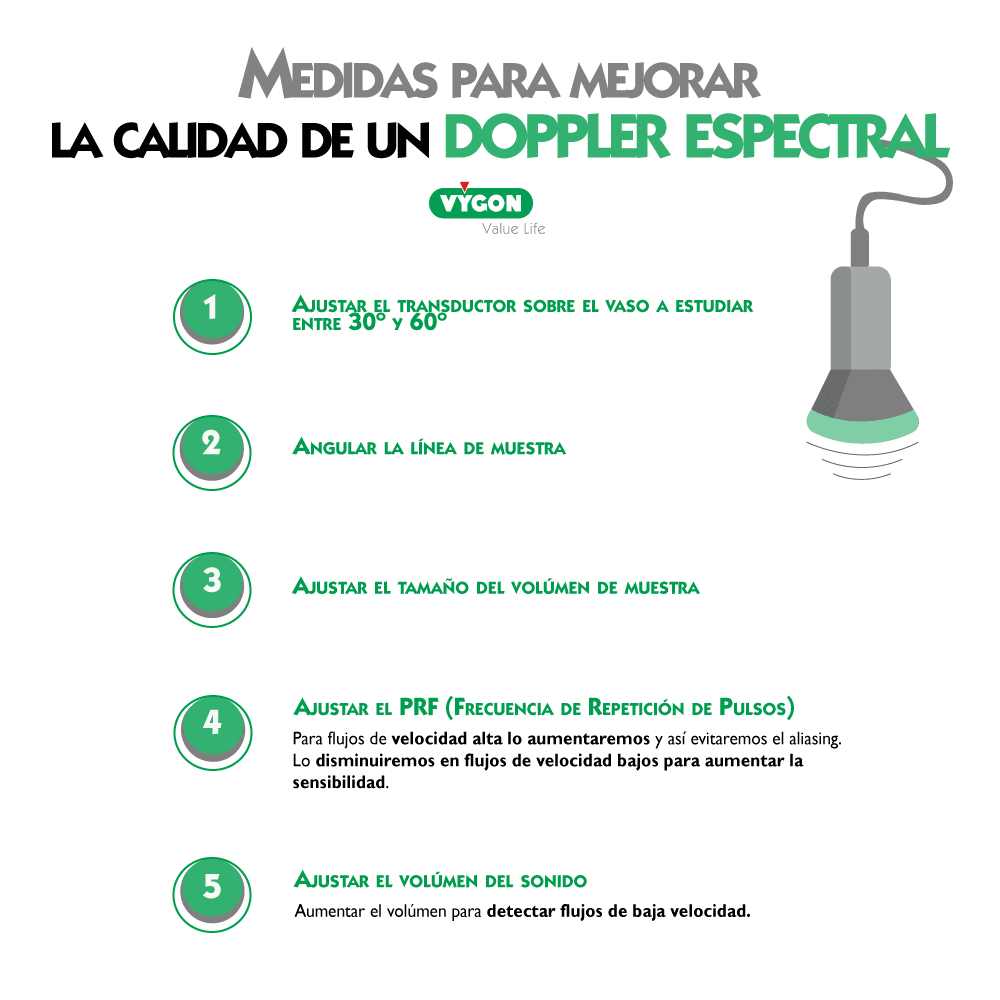

4. Cómo mejorar la calidad del análisis del doppler espectral

También existen varias manipulaciones y ajustes que puede hacer el operador para poder mejorar el análisis del doppler:

Manteniendo la exploración en modo B, activamos el modo doppler espectral. A continuación, colocamos el volumen de muestra (identificado como dos líneas paralelas y perpendiculares al eje del haz de ultrasonidos) en el interior del vaso que se pretende estudiar. El tamaño del volumen de muestra debe ser proporcional al calibre del vaso a estudiar.

Angulamos el transductor entre 30 a 60º o bien hacia la parte distal del cuerpo (hacia la mano) o hacia la parte proximal (hacia la cabeza), y por último volvemos a activar el modo doppler espectral para que comience el análisis de velocidades.

Si el espectro de velocidades se sitúa sobre la línea base significará que el flujo del vaso sanguíneo estudiado se dirige hacia el transductor. Por el contrario, si el espectro de velocidades se sitúa por debajo de la línea de base, significará que el flujo del vaso sanguíneo estudiado se alejará del transductor.

Además del sentido de la sangre, la morfología del espectro nos informará del carácter del flujo del vaso estudiado. Así, si el flujo es pulsátil, habitualmente se tratará de un vaso arterial. Mientras que si el flujo es continuo o poco pulsátil, habitualmente se tratará de un vaso venoso.